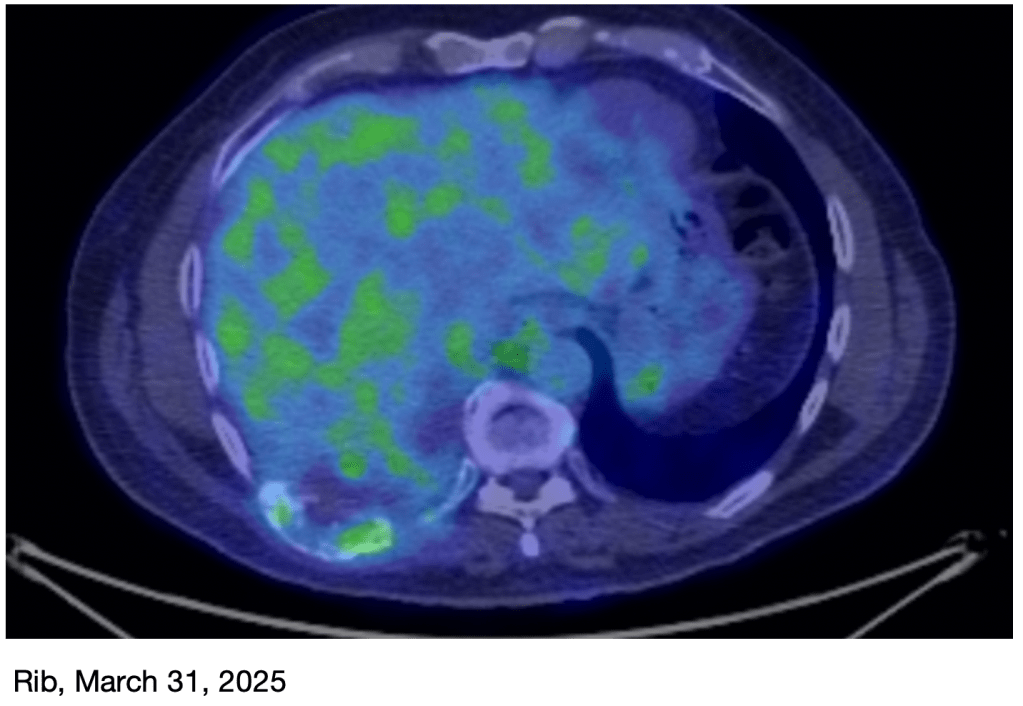

March PET Scan: I just had a new PET scan on Monday, and the results are great! The tumor on my rib is basically gone, and the primary tumor in my lung is now very small, just a faint reminder of what it was! This is obviously great news! I’ll have another scan in June.